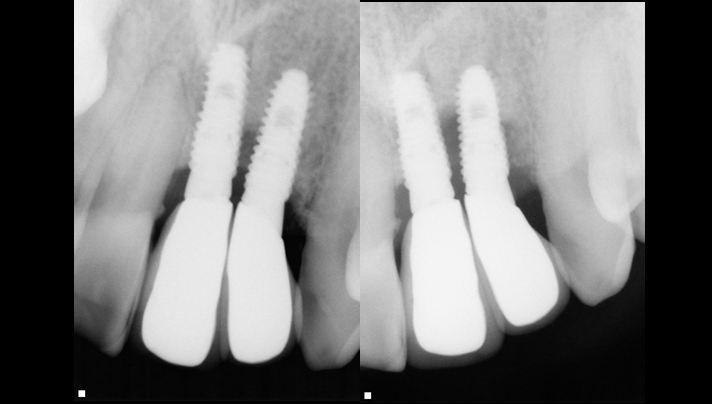

Clinical case: Peri-implantitis treatment case using titanium or NiTi brush

- Courtesy of Dr. Dae-Hee Lee, South Korea -

Dr. Dae-Hee Lee,Maxillary Anterior,Peri-implantitis,Bone regeneration,Aesthetic zone,#21,#22,GBR,Titanium Brush Set